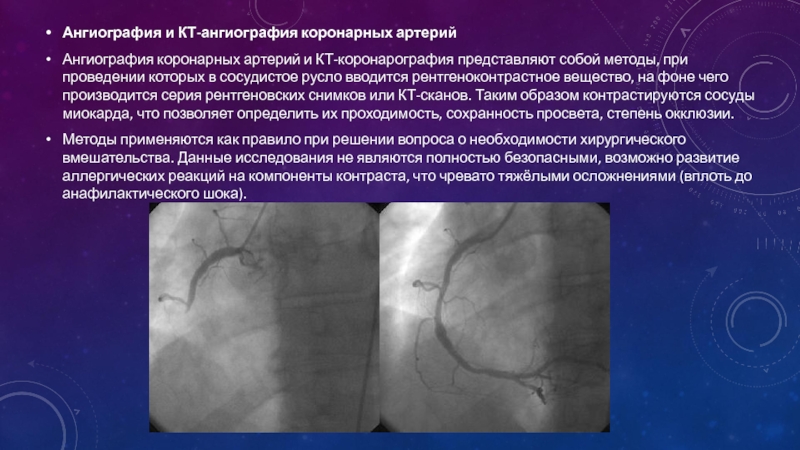

Раздел: Снимки успеха